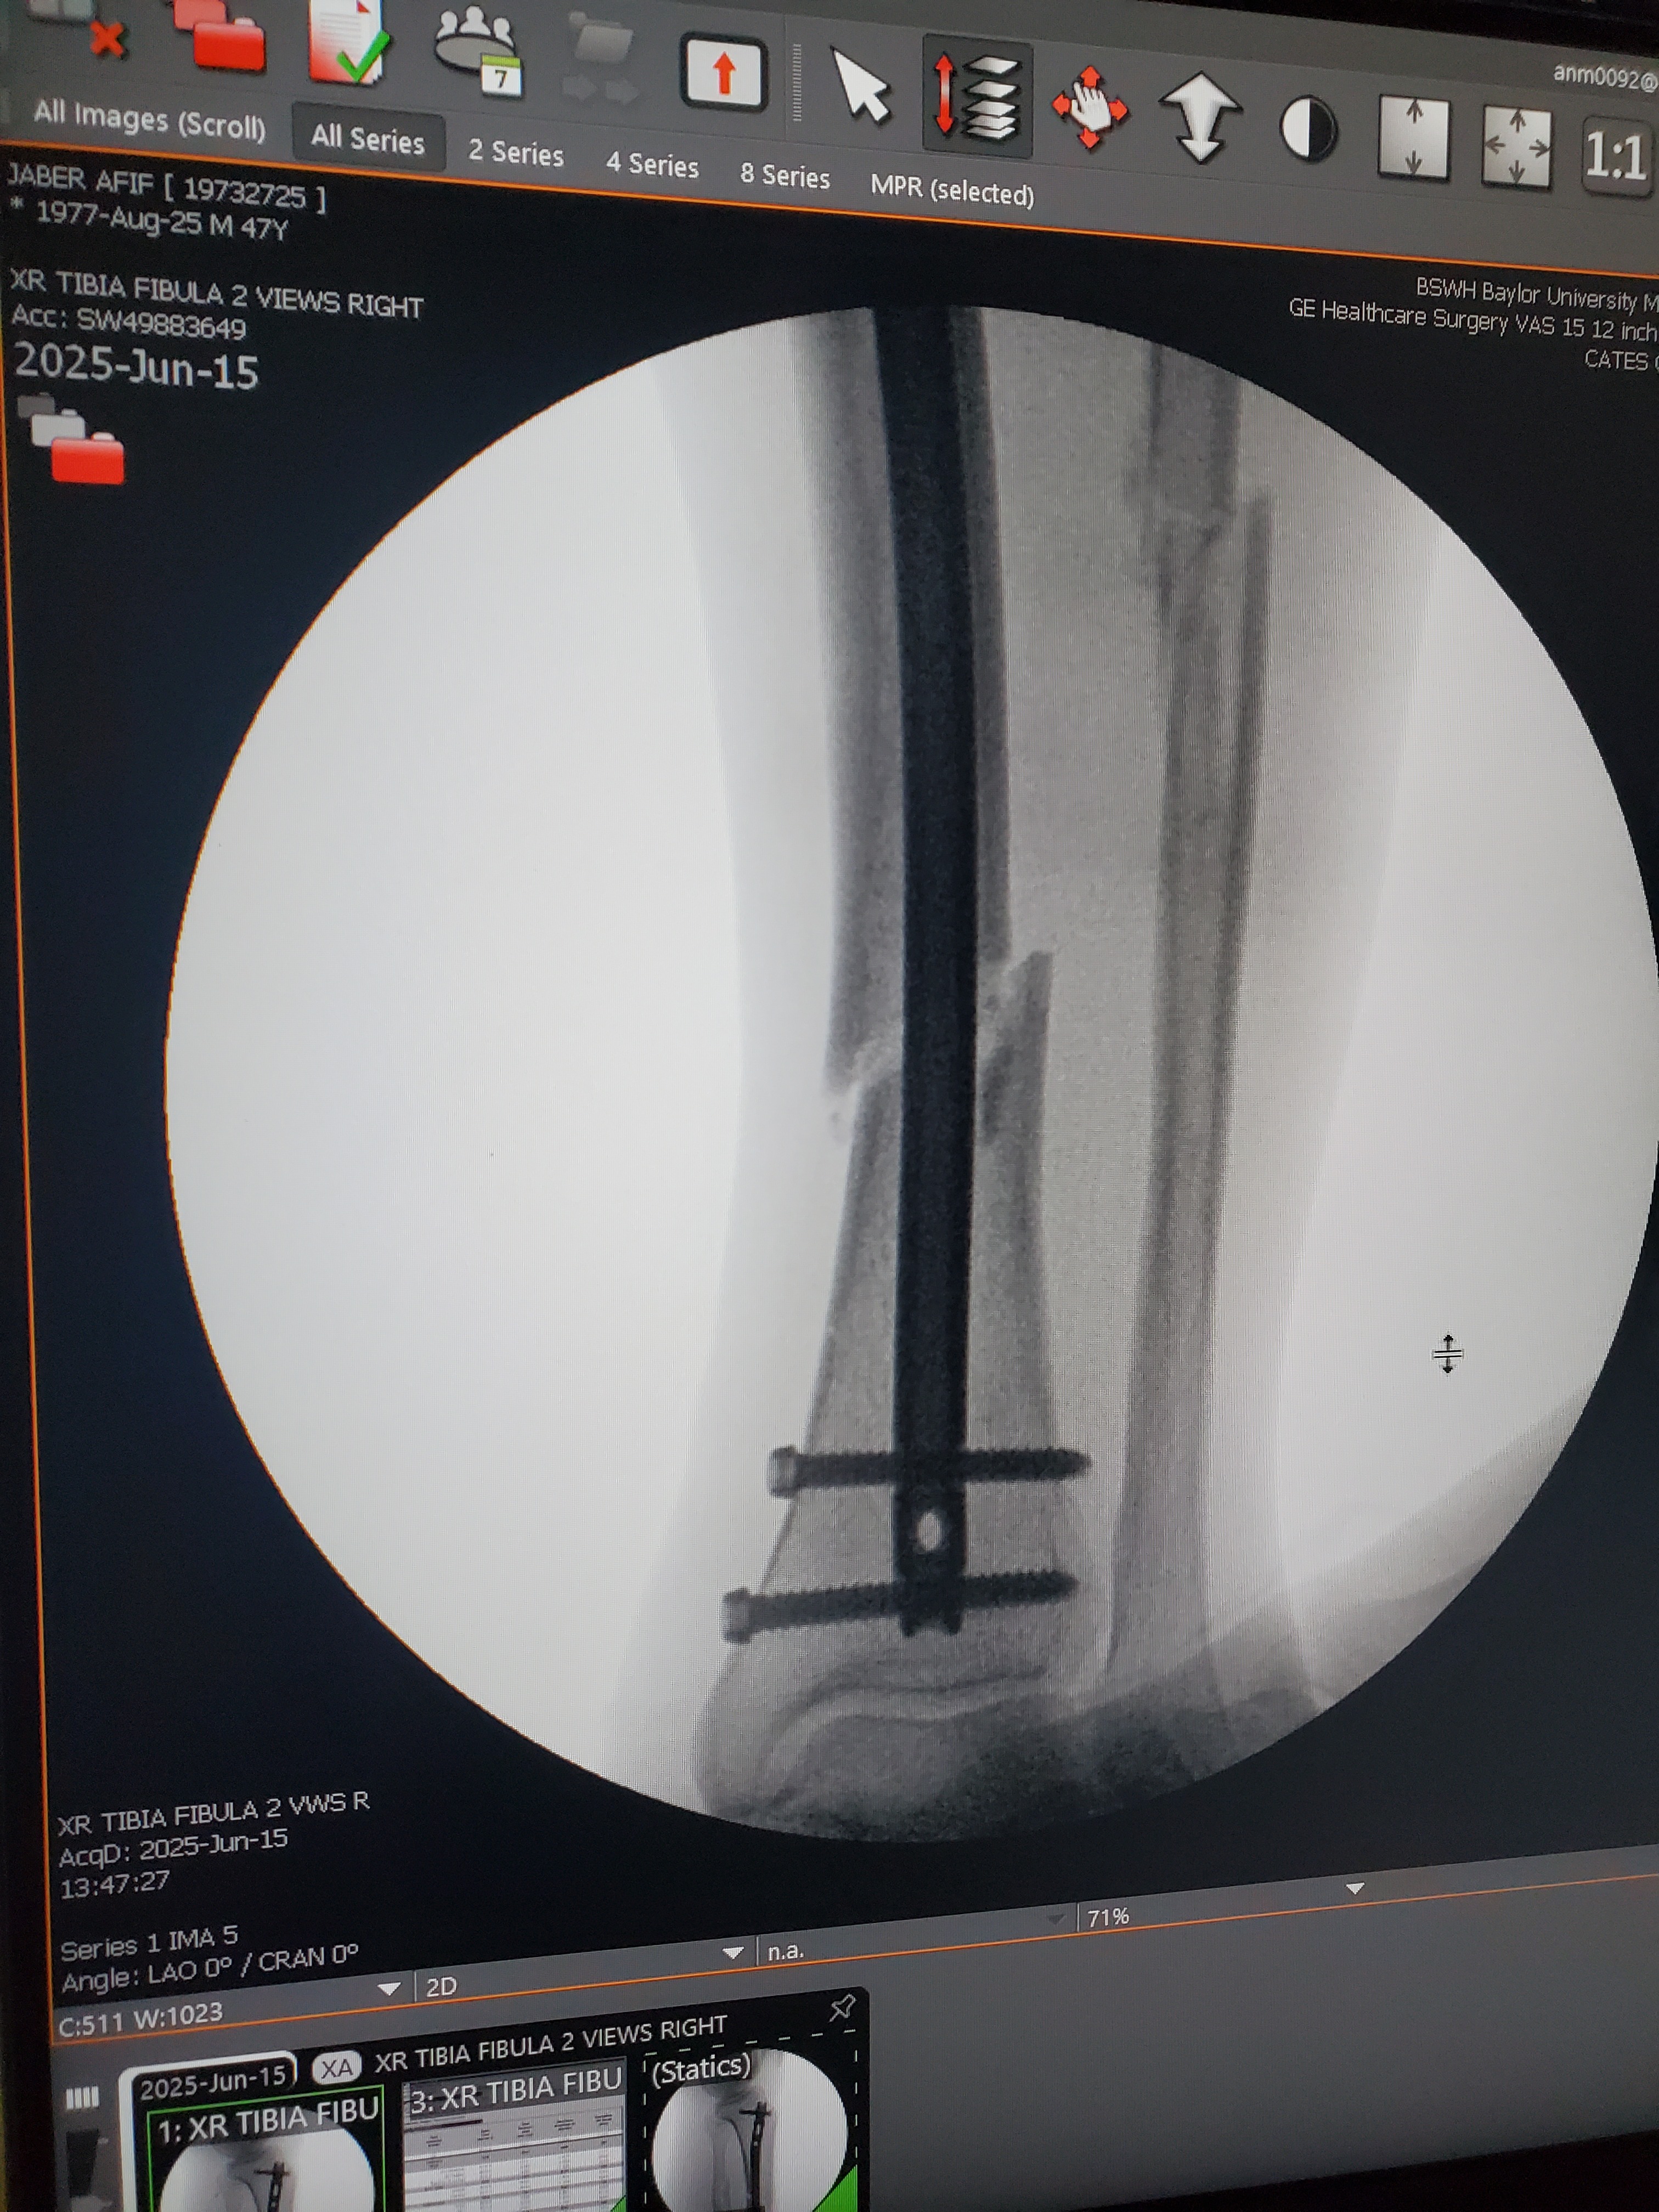

- A

Good afternoon, my name is Afif Jaber, but I'm commonly known as AJ, and I come seeking assistance in this time of an unexpected health emergency stemming from an almost tragic accident on 6/14/25, during which time I had my left leg broken in multiple sections. This accident has unfortunately brought an immense and sudden pileup of medical bills and financial hardship as I'm currentlyunableto work as I heal and look forward to going into therapy. I'd appreciate any and all assistance that I can get as blessed upon your abilities to give towards this urgent request for help and thanking each and everyone in advance for your kind donation. I also accept donations through my CashApp handle $AJHustle77. God bless.